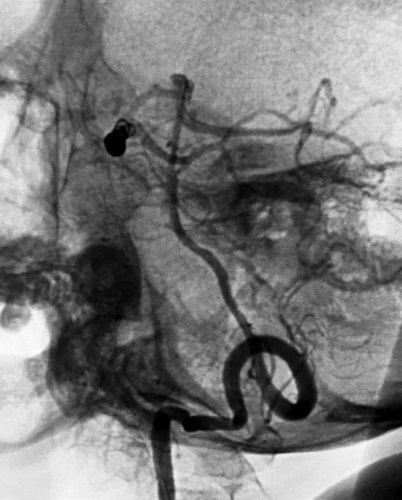

先微导管Echelon到位右侧大脑后动脉瘤,小心成篮,在保留大脑动脉通畅情况下尽可能地多栓塞动脉瘤体部与顶部,对瘤颈的栓塞不强求;分别为Presidio 3D 5mmX17cm,EV3 3D 3mmX6cm,3mmX4cm,2mmX4cm,在观察形态学弹簧圈对载瘤动脉无明显影响后实行解脱,最后造影见右侧大脑后动脉动脉瘤顶端不显影,近端于瘤颈处仍有部分显影。 之后再退至基底动脉瘤内,行部分栓塞,EV3 3D 4mmX8cm,2mmX4cm, 1.5mmX2cm,1.5mmX2cm,不用支架,是因为考虑病情较重,脑室较大,术后可能要行脑室外引流术,而支架应用则需用双抗会造成手术操作困难。后期拟再行补救支架手术。

首先栓晒右侧大脑后动脉瘤

右侧大脑后动脉瘤术后侧像

在处基底动脉瘤术后正侧位像